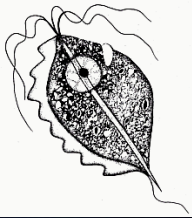

Chilomastrix mesnili (troph)

Chilomastix mesnili (troph)